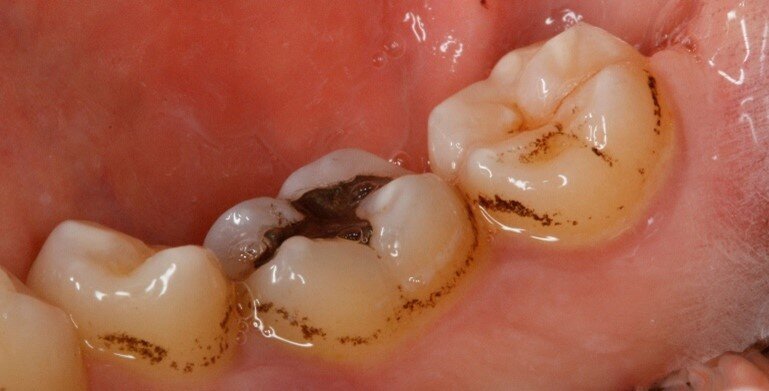

Il secondo paziente è un uomo di anni 55 con anamnesi negativa, che non assume farmaci e non fuma. All’esame obiettivo si notano immediatamente black stains molto evidenti sui versanti vestibolari dei denti posteriori. Si procede con la raccolta della documentazione fotografica, la rilevazione dell’indice di placca attraverso l’utilizzo del rivelatore di placca e la compilazione della cartella parodontale. Dall’analisi dei dati raccolti si deduce che il paziente ha sofferto in passato di parodontite e ha affrontato terapia parodontale non chirurgica per stabilizzare la situazione parodontale. Ad oggi il parodonto è stabile e l’igiene è discreta (IP=30%). Vengono raccolti in una tabella riassuntiva anche i dati relativi alla presenza di black stains. Si prosegue con la motivazione e l’istruzione ad un’accurata igiene orale domiciliare e si sottopone il paziente ad una seduta di igiene orale professionale. Dopo aver effettuato la seduta di igiene professionale si chiede al paziente di cambiare testina allo spazzolino elettrico in uso e di assumere “Lautoselle” una volta al giorno per i tre mesi successivi. Il paziente viene controllato dopo un mese e quindi al termine di questo periodo di assunzione del probiotico, vengono nuovamente scattate delle fotografie e compilata la tabella riassuntiva per monitorare la formazione delle black stains. Nonostante il miglioramento dell’igiene orale domiciliare, visti anche gli impegni personali e lo stile di vita del paziente stesso, si decide di procedere ad un deplaquing con polveri di glicina per mantenere lo stato di salute orale del paziente e di interrompere lo studio.

Durante la prima raccolta dati sono stati rilevati 31 siti totali che presentavano black stains (Tab. 4), 13 siti nel controllo ad un mese dall’inizio dell’assunzione di “Lautoselle” (Tab. 5), infine, 18 siti una volta terminata l’assunzione di “Lautoselle” (Tab. 6); di questi ultimi tutti i siti che presentano black stains sono di primo grado e molto meno evidenti rispetto alla prima raccolta dati. Rispetto al caso precedente i risultati sono stati meno soddisfacenti: i siti che presentano black stains corrispondono al 55,8% rispetto a quelli iniziali già al termine del periodo di assunzione di “Lautoselle”. Va in ogni caso considerato che i pigmenti presenti sono molto evidenti e che, per ammissione del paziente stesso, l’assunzione del probiotico non è stata scrupolosa (Figg. 5a-5c).

Fig. 5a - Fotografia del quarto sestante linguale al primo rilievo delle black stains.

Fig. 5b - Controllo dopo un mese.

Fig. 5c - Controllo a tre mesi.

Rispetto al caso precedente i risultati sono stati meno soddisfacenti: i siti che presentano black stains corrispondono al 55,8% rispetto a quelli iniziali già al termine del periodo di assunzione di “Lautoselle”. Va in ogni caso considerato che i pigmenti presenti sono molto evidenti e che, per ammissione del paziente stesso, l’assunzione del probiotico non è stata scrupolosa.